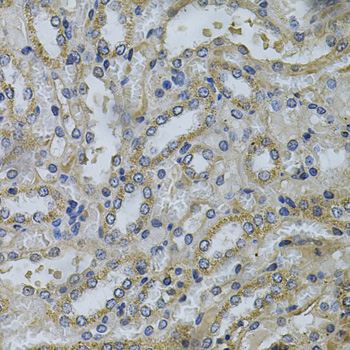

Immunohistochemistry of paraffin-embedded mouse kidney using SERPINE2 Antibody. |